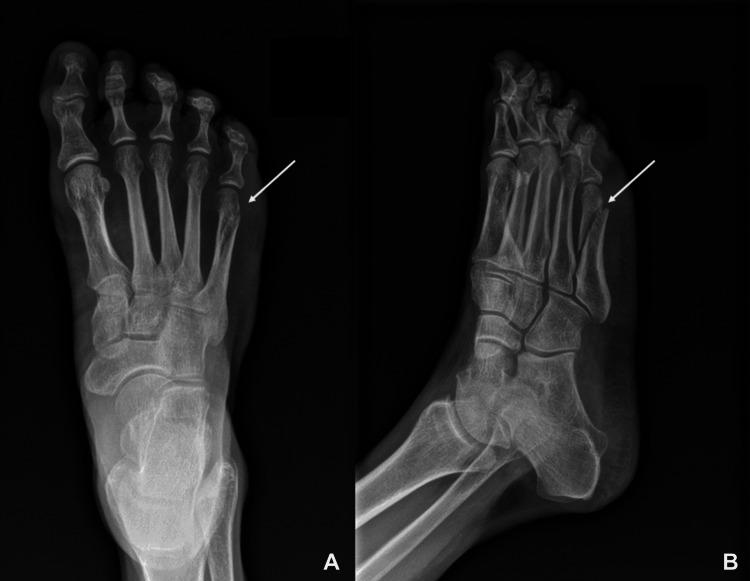

This case report identifies typical manifestations of a patient with hypophosphatasia, a rare genetic condition in which mutations in tissue-non-specific alkaline phosphatase (TNSALP) enzymes cause low levels of alkaline phosphatase and defective bone mineralization. It explores common diagnostic clues from the history and laboratory evaluation, which can help clinicians identify the disorder. This case introduces a 49-year-old patient with a long history of fractures and dental abnormalities who was referred to endocrinology for evaluation of osteopenia. Further review of her laboratory data was noteworthy for a low level of alkaline phosphatase. Additionally, a low vitamin B6 level was measured, and genetic testing was ultimately diagnostic for hypophosphatasia. The patient was started on the anabolic agent teriparatide but was lost to subsequent follow-up. This case discusses additional management considerations, which are currently limited but continue to evolve, and cautions against bisphosphonate use in the setting of hypophosphatasia.